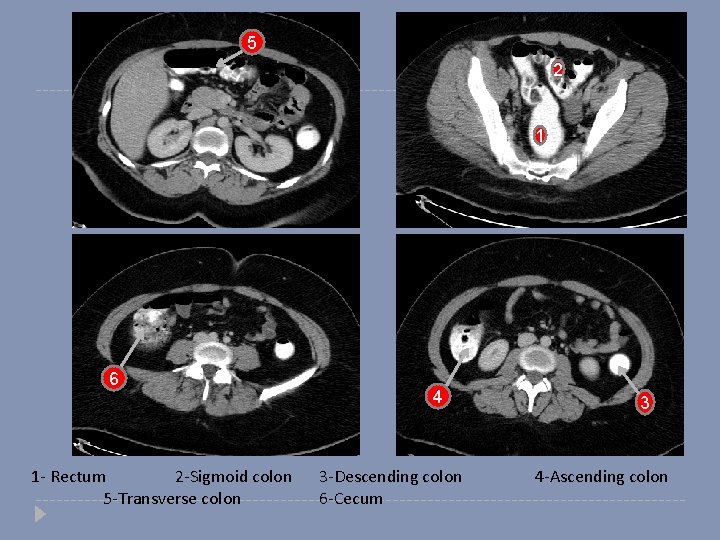

5 2 1 6 1 - Rectum 2 -Sigmoid colon 5 -Transverse colon 4 3 -Descending colon 6 -Cecum 3 4 -Ascending colon